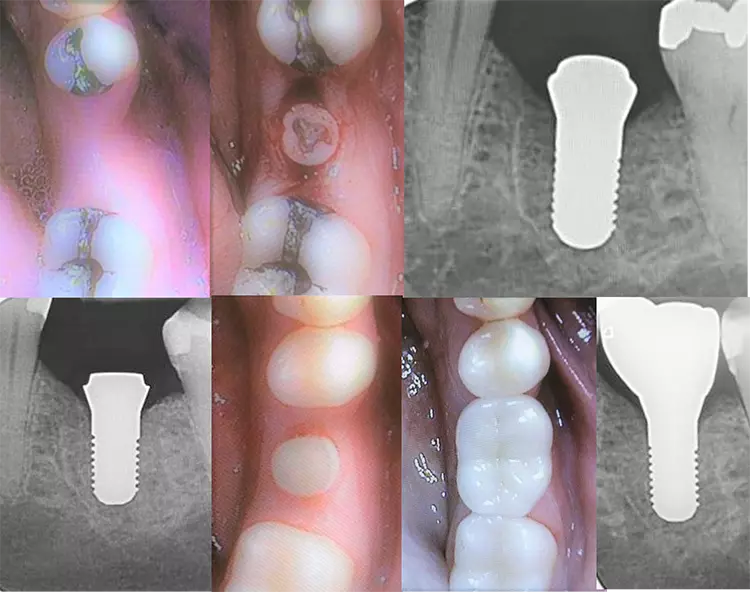

Patientenfall Spätimplantation

Im Fall wurden Spätimplantate in regio 44 und 46 gesetzt. Das Abutment mit seinen durchdachten Emergence Profiles (EP) von ø 5,2 mm beim ø 4,1 Patent und EPs von ø 6,3 mm bei Patents™ ø 4,5 und ø 5,0 mm ist bereits im Patent™ Implantat integriert. Nach 3- bis 4-monatiger „Biointegration“ (Hart- und Weichgewebe) wird der Post-Aufbau, der aus einer speziellen medizinischen Glasfaser besteht, mit Relyx Unicem (3M Espe) ohne Bonding/Silansysteme eingeklebt, leicht präpariert, abgeformt und der Zahnersatz wie bei einer Zahnkrone eingesetzt (Abb. 2-8).